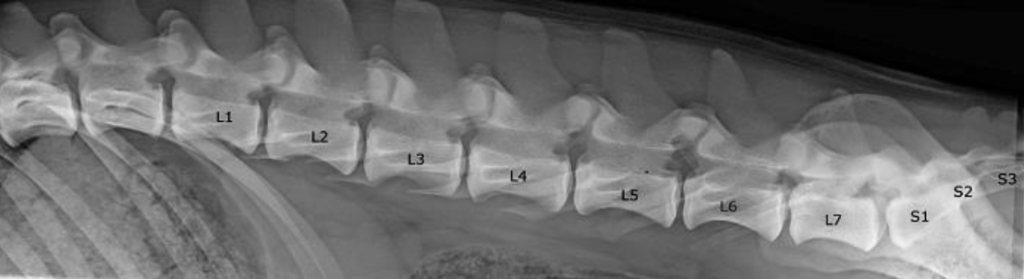

Een LTV oftewel een “lumbosacrale overgangswervel” (afkorting van de Engelse benaming “Lumbosacral Transitional Vertebrae”) is een aangeboren en erfelijke afwijking van de wervelkolom, deze aandoening kent verschillende gradaties. LTV wordt door Finland ingedeeld in de volgende vier gradaties LTV 1-2-3-4, elke gradatie benoemd een andere afwijking, één hond kan verschillende gradaties hebben (bijvoorbeeld een LTV2 + LTV4). Een LTV bevindt zich tussen de laatste normale lendenwervel (LNLV) en de eerste normale sacrale wervel (FNSV). Een LTV kan kenmerken hebben van een lendenwervel en een sacrale wervel, en kan zowel symmetrisch als asymmetrisch zijn.

Hieronder leg ik o.a. de verschillende gradaties LTV uit:

LTV0: normaal

De hond heeft in dit geval geen afwijking en krijgt de beoordeling LTV0

LTV1: onderbroken sacrale kam

Een normale sacrale kam (spinaaluitsteeksel van het heiligbeen) is gevormd uit drie sacrale wervels, de S1-S3. Bij een hond zonder afwijking aan het heiligbeen zijn deze drie wervels inclusief spinaalsuitsteeksel (sacrale kam) volledig aan elkaar versmolten (fused), bij een hond met een LTV1 afwijking is dit niet het geval. Bij de aandoening LTV1 is de sacrale kam niet goed/volledig aan elkaar versmolten, we spreken dan van een “onderbroken sacrale kam”, in de meeste gevallen bevindt zich dit tussen de S1 en de S2. Andere vormen van een LTV1 zijn:

– het eerste deel van de sacrale kam is onvolledig ontwikkeld, het wervellichaam van het sacrum is altijd volledig versmolten;

– verandering aan de laatste lendenwervel richting sacralisatie gaat. De L7 is meestal korter en ligt meer caudaal, het dwarsuitsteeksel kunnen er anders uitzien dan normaal;

– het heiligbeen bestaat uit vier wervels S1-S4, in de plaats van de normale S1-S3, de eerste staartwervel (Cd1) is versmolten met het heiligbeen;

– het heiligbeen bestaat uit twee wervels S1-S2, in de plaats van de normale S1-S3, de S3 is dan niet versmolten met de S1-S2.

LTV2: symmetrische lumbrosacrale wervel

Bij een LTV2 heeft de hond een aandoening aan de ‘laatste’ wervel. Deze wervel kan kenmerken hebben van zowel een lendenwervel als een sacrale wervel. Deze wervel is vaak korter en ligt meer caudaal (naar beneden). De dwarsuitsteeksels van zo’n wervel liggen vaak lateraler dan normaal. Bij een LTV2 is deze wervel symmetrisch, hetzelfde aan beide kanten (ten opzichte van een LTV3 waar deze asymmetrisch is). In sommige gevallen komt het ook voor dat de laatste wervel abnormaal is versmolten aan de sacrale kam.

LTV3: asymmetrische lumbrosacrale wervel

Bij een LTV3 heeft de hond een aandoening aan de ‘laatste’ wervel. Deze wervel kan kenmerken hebben van zowel een lendenwervel als een sacrale wervel. Deze wervel is vaak korter en ligt meer caudaal (naar beneden). De dwarsuitsteeksels van zo’n wervel liggen vaak lateraler dan normaal. Bij een LTV3 is deze wervel asymmetrisch en ziet er aan beide kanten anders uitzien, de linkerkant kan bijvoorbeeld meer kenmerken hebben van een sacrale wervel en rechterkant van een lendenwervel. LTV3 wordt vaak gezien als de meer extreme versie van een LTV2. In sommige gevallen komt het ook voor dat de laatste wervel abnormaal versmolten is aan de sacrale kam.

LTV4: 6 of 8 lendenwervels

Een normale wervelkolom van een hond bestaat o.a. uit zeven lendenwervels L1-L7 (lumbale wervels) en drie sacrale wervels S1-S3 (sacrale kam). Bij een hond met een LTV4, hebben ze maar zes lendenwervels (L6) of een extra achtste lendenwervel (L8). Wanneer de eerste sacrale wervel (S1) dezelfde kenmerken heeft als een lendenwervel spreken we over lumbalisatie. Wanneer de L7 volledig versmolten is met de sacrale kam (S1) en de L6 de laatste normale lendenwervel is spreken we van sacralisatie.

Het abnormale aantal lendenwervels gaat soms nog gepaard met een andere gradatie LTV (LTV1-3).

NOTE: Voor het beoordelen van een LTV4 is één laterale röntgenfoto nodig waarop de laatste borstwervel (T13) tot de eerste staartwervel (Cd1) te zien zijn. De bovenstaande twee foto’s laten zien wanneer het om lumbalisatie of sacralisatie gaat.

Hoe wordt een LTV gediagnosticeerd?

Voor het beoordelen van een LTV worden een aantal röntgenfoto’s gemaakt:

- Een laterale röntgenfoto waarop de laatste borstwervel T13 (Thoracale wervel) te zien is tot en met de eerste staartwervel Cd1 (Coccygeale wervel). Oftewel een T13-Cd1 röntgenfoto.

- Ook wordt er een ventrodorsale röntgenfoto gemaakt waarop minimaal de laatste twee lendenwervels + het volledige sacrum te zien is.

- Bij voorkeur ook nog een laterale foto waarop de laatste halswervel C7 (Cervicale wervel) tot en met de eerste lendenwervel te zien is. Oftewel een C7-L1 röntgenfoto. Deze röntgenfoto is geen eis voor het beoordelen van een LTV, maar wel gewenst.

Deze eisen stelt Finland (Finnish Kennel Club) o.a. om de hond te kunnen beoordelen, verdere uitleg is te vinden via deze link “how to take LTV radiographs”.